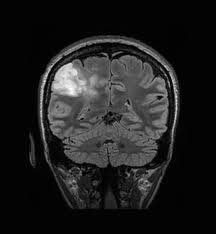

There aren't many alternatives for treating glioblastoma multiforme, a type of brain cancer. Among the available treatment options are immunotherapy, chemotherapy, radiation, surgery, and targeted therapy. Adults are more likely to be diagnosed with this type of cancer, so there is a strong desire for better therapies. New research, business partnerships, and more healthcare financing are all contributing to the market's growth. But there are other problems, such as expensive, ineffective, or negatively affecting remedies. Scientists are working diligently to create more potent therapies for glioblastoma, a type of brain cancer.

The prevalence of glioblastoma, a type of brain cancer, in adults is rising, which is increasing the cost of treatment. People seek improved treatments to extend their lives and improve their chances of surviving cancer. Due to increased research, business alliances, and international funding for healthcare, the industry is growing to satisfy this demand. Currently, doctors are customizing glioblastoma treatments based on the genetic composition of each patient and the specific characteristics of their tumor. New technologies have made it easier for them to understand these nuances. This individualized approach improves treatment efficacy and reduces adverse effect risk.